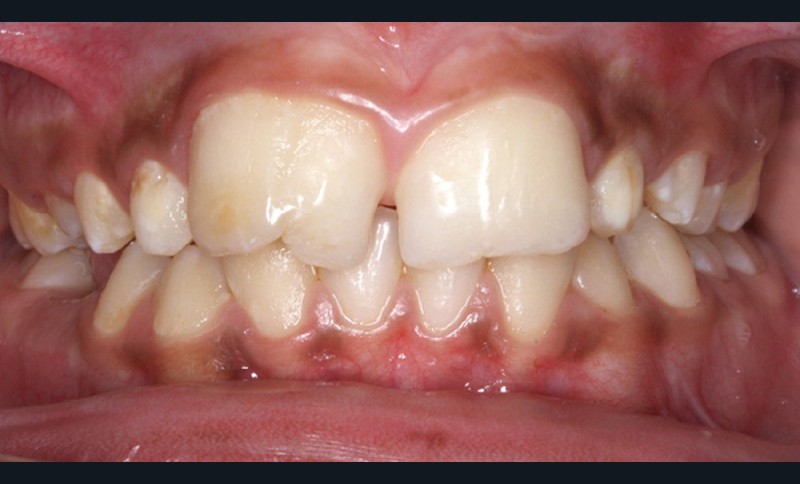

Antony, 11 ans se présente initialement pour une demande esthétique concernant ses deux incisives centrales qu’il trouve trop grosses (fig. 1a-c).

Le profil est convexe et associé à une inocclusion labiale au repos. Il s’agit d’une classe II squelettique sur un schéma facial normodivergent. Les rapports occlusaux sont de classe II bilatérale (complète au niveau molaire) avec des incisives inférieures vestibulo-versées. La 21 est géminée et la 11 vraisemblablement fusionnée avec un germe surnuméraire, sans altération de la formule dentaire. Du fait du diamètre mésiodistal fortement augmenté des incisives centrales, et du manque de place à l’arcade maxillaire qui en découle, les 12 et 22 sont en inversé d’occlusion en palato position. Les 53 et 63 sont persistantes sur l’arcade avec une inclusion en transposition incomplète de la 13, dont la cuspide se situe entre la racine de la 12 et celle de la 11 résorbée (fig. 1d-g).